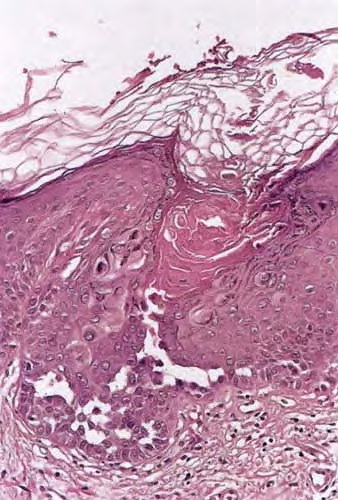

pyknotic nucleus that is surrounded by a clear halo. By virtue of size and the conspicuous halo, corps ronds stand out clearly . Peripheral to the halo lies basophilic dyskeratotic material as a shell . The nonstaining halo in some instances is partially replaced by homogeneous, eosinophilic dyskeratotic material . Compared with the corps ronds, the grains are much less conspicuous. They resemble parakeratotic cells but are somewhat larger. The nuclei of grains are elongated and often grain shaped and are surrounded by homogeneous dyskeratotic material that usually stains basophilic but may stain eosinophilic. The lacunae represent small, slitlike intraepidermal vesicles most commonly located directly above the basal layer. They contain acantholytic cells and show premature partial keratinization. Because of shrinkage, some of them are elongated, and these then appear identical with the grains in the horny layer. The villi projecting into the lacunae may be quite tortuous, so on histologic examination, some of them appear in cross section as rounded dermal structures lined by a solitary row of basal cells .

In hypertrophic lesions of Darier’s disease, considerable acanthosis may occasionally be observed, either as proliferations of basal cells or as pseudocarcinomatous hyperplasia. Proliferations of basal cells consist of long, narrow cords composed of two rows of basal cells separated by a narrow lacunar space

The vesiculobullous lesions, which occur in rare instances, differ from lacunae merely in size; they contain numerous shrunken cells with the appearance of grains .